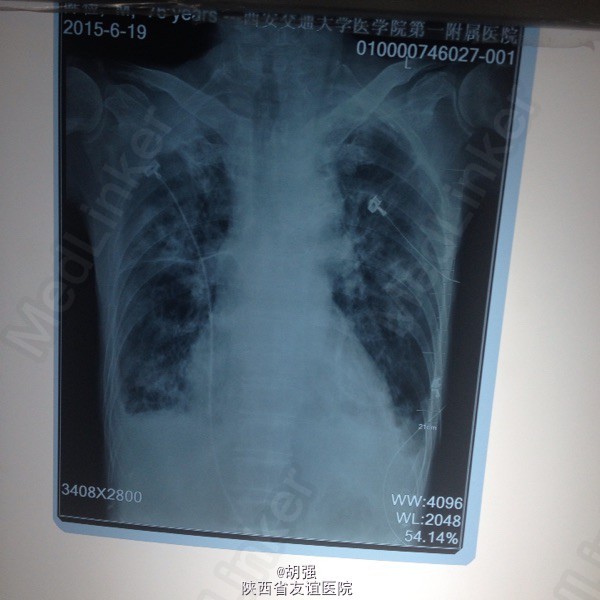

老年男性患者七十六岁。 主诉:反复咳嗽、咳痰10年,加重2月。 现病史:患者10年前受凉后出现咳嗽、咳痰,于当地医院给抗感染治疗后症状消失。此后每遇劳累或者季节交替时,反复出现咳嗽、咳痰、胸闷、气短,且逐年加重,多次住院,行胸部CT、肺功能、血气分析等相关检查,诊断为:慢性阻塞性肺疾病急性加重期,给于抗感染、平喘治疗后均能缓解(具体用药及剂量不详)。2月前受凉后,咳嗽、咳痰、气短症状加重,咳大量白色黏痰,于外院抗感染对症治疗效果不佳,遂来我院。 既往有甲状腺功能亢进病史8年,继发心房纤颤,行I131治疗;有腔隙性脑梗死病史5年。

查体:口唇略紫绀,口腔黏膜无充血、糜烂、溃疡;颈静脉怒张,桶状胸,两侧呼吸动度及语颤减弱,叩诊呈过清音,两肺呼吸音粗糙,可闻及哮鸣音及湿性啰音。心率110次/分,律不齐,心音强弱不等,各瓣膜听诊区未闻及病理性杂音。腹平软,无压痛,肝脾肋下未及,双下肢水肿。 血常规: 白细胞14.01XE9/L、中性细胞比率91%、血红蛋白170g/L、血小板370X10E9/L。

慢性阻塞性肺疾病急性加重期,肺结核?肺真菌病?支气管扩张?慢性肺源性心脏病,心功能IV级,甲状腺功能亢进症,I131治疗后,心房纤颤,脑梗死。 外院给予特治星及氟康唑治疗效果不佳。入院后给予舒普深3.0静注2次/日联合莫西沙星片o.4口服1次/日,多索茶碱0.2十甲泼尼龙20mg2次/日,镁极化液250ml十异舒吉20mg静点,酚妥拉明10mg静点及强心、利尿治疗后好转。